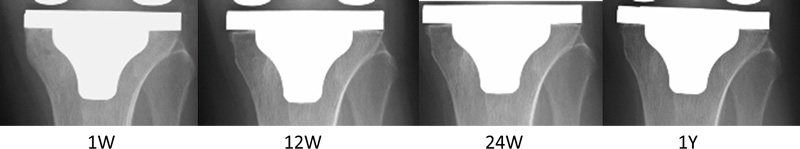

内側領域の骨密度は、PA群において術後2週と比し、1.5年にかけて有意に漸減していった。RE群では、内側領域において低下することなく維持されていた。2機種間の比較では、術後1年および1.5年時には、PA群はRE群に比して有意に骨密度が低下していた(図5a)。外側領域では、PA群では経過中増減はなかったのに対し、RE群では術後6ヶ月で有意に上昇し、その後維持されていた(図5b)。キール先端領域では、PA群もRE群においても骨密度は術後有意な増減はなかった(図5c)。X線学的検討では、骨密度低下を来す内側領域において術後早期に0.5~1mm程度の隙間が出来る。そしてそれは、2年までに全例骨侵入が起こり埋まっていった(図6)4)

cv_hachiya_01_06_02.jpg

図6b. 75歳女性 右TKA

両症例とも1~2mmのRadiolucent lineが出現したが、徐々に縮小し埋まる。